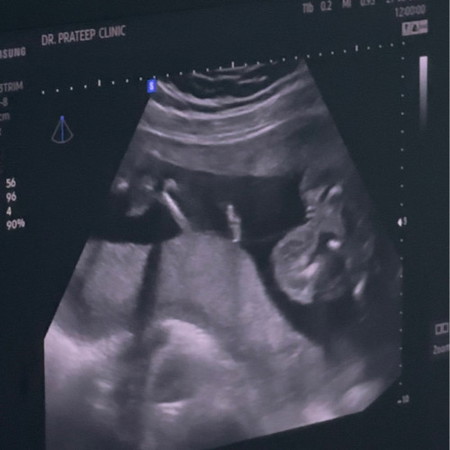

แม่ๆช่วยดูหน่อยค่ะ

คุณหมอบอก ผู้หญิงแบบนี้ชัดเจนไมค่ะ น้องหนีบขาคุณหมอดูด้านล่างตอนนี้20+5วีคค่ะ

อาจจะเพราะหนีบขาอยู่รึเปล่าคะ มีลุ้นชายได้อยู่นะคะ